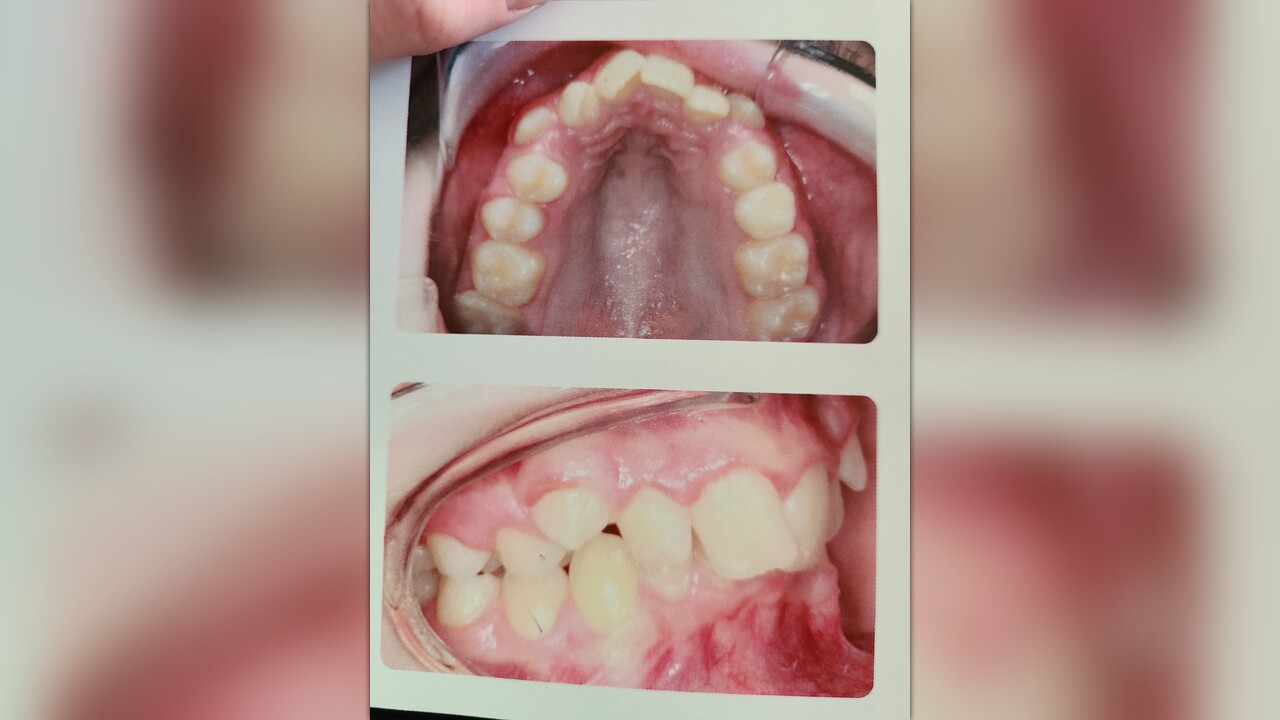

My son is 12 and has been suffering lots of pain and infections in his mouth and eating has been a challenge for him, we found out yesterday it's because he has an underdeveloped lower jaw and his bottom front teeth are literally bitting into the roof of his mouth. You can see by the pictures his front top teeth are 100% covering his bottom teeth. He needs extensive work done in order to get him out of pain, stop infections and get him gaining weight again. Unfortunately I'm a full time student and working overnight which just barely covers rent and bills. Trying to raise at least the 425 to get his molds done and the 750 (down payment and 1st months) to get them put on. If he doesn't get it done before he hits puberty which is coming soon he will have to have his jaw broken and wired shut and will likely have to be tube feed due to him already being only 60lbs at 5'3 and then even after surgery braces at that point will be closer to 20grand.